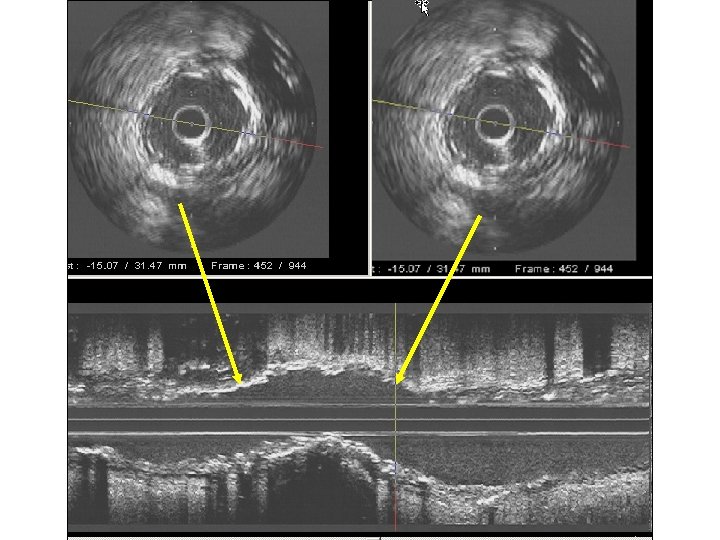

Concentric calcification with broken arcs: No need for Rotablator

Stent at 12 atm. Stent at 20 atm.